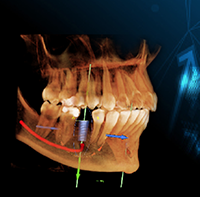

Grand Design: Implant and Full-Arch Solutions for Strength and Stability

Wednesday, November 18, 2020

Implant therapy has become an integral part of clinical dentistry, with ever-increasing numbers of patients seeking this treatment. However, this good news comes with a significant challenge: patients have increasing expectations for shortened treatment duration - even patients with anatomical deficiencies. You need serious treatment flexibility to create optimal outcomes for all indications. Learn more about advanced system options in this new eBook.